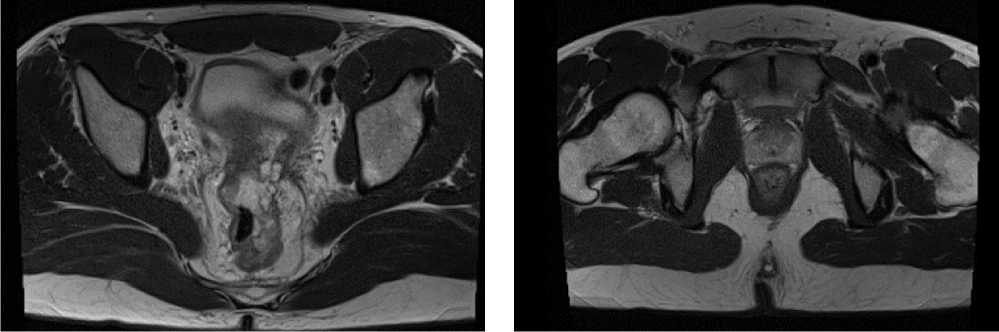

С ноября 2022 г. выполнено 14 введений пембролизумаба с максимальным эффектом частичный регресс (образование между передней поверхностью прямой кишки и задней поверхностью предстательной железы регрессировало полностью). По результатам контрольных обследований (КТ ОБП и МРТ ОМТ от сентября 2023 г.) сохраняются очаги в печени до 21 × 11 мм, а также опухоль средне- и верхнеампулярного отделов прямой кишки с выраженным муцинозным компонентом. МР-стадия Т4а (CRM+, EMVI+) (рис. 9, 10).

Рис. 9. Частичный регресс, по данным компьютерной томографии органов брюшной полости, на фоне иммунотерапии пембролизумабом у пациента 38 лет с диагнозом метастатический колоректальный рак с признаками микросателлитной нестабильности (сентябрь 2023 г.)

Fig. 9. Partial response according to abdominal CT scan data during immunotherapy with pembrolizumab in a 38-year-old patient with metastatic MSI-H colorectal cancer (September 2023)

Рис. 10. Частичный регресс, по данным магнитно-резонансной томографии органов брюшной полости, на фоне иммунотерапии пембролизумабом у пациента 38 лет с диагнозом метастатический колоректальный рак с признаками микросателлитной нестабильности; МР-стадия Т4а (CRM+, EMVI+) (сентябрь 2023 г.)

Fig. 10. Partial response according to abdominal magnetic resonance imaging during immunotherapy with pembrolizumab in a 38-year-old patient diagnosed with metastatic MSI-H colorectal cancer; MR stage T4a (CRM+, EMVI+) (September 2023)